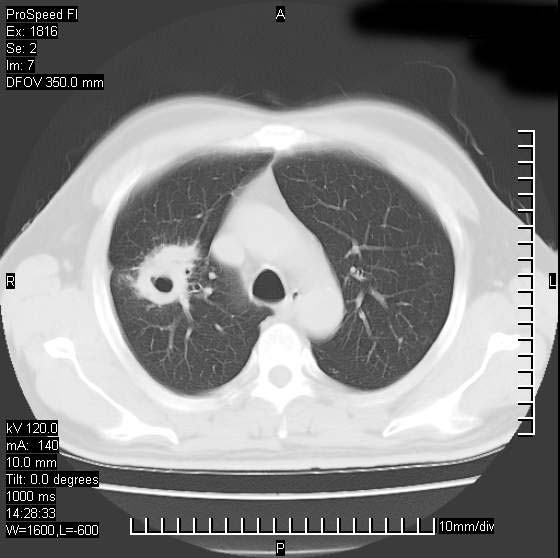

男性,50 ,肺结核9年,咳嗽,胸痛一周。右上肺见一厚壁空洞,周边有点样钙化,胸膜牵拉,洞壁较光整。诊断结核性空洞。有癌性的可能吗? 余肺野无异常,没有上传。

洞壁较厚内壁比较光整,考虑结核性空洞,最好再取原片比较下或薄扫一下

洞壁较厚内壁比较光整,两个病灶有关联性,纵隔淋巴结不大,考虑结核性空洞。

结核有可能,肺癌待排。空洞的前上还方见一软组织结节影。

部分层面见空洞为近似新月形,洞壁内缘尚规整且近肺门侧,周围见索条影、卫星灶,结合病史,首先考虑肺tb可能大。

9年的结核应该呈现多形态病灶,该病例只能见到少许纤维索条影,似乎与结核的演变不太相符。空洞内壁不光整,外侧伴有胸膜粘连,考虑癌性空洞可能性大,期待结果。

内壁光滑,周围有卫星灶,还是结核可能性大,但壁太厚,应密切观察随访复查